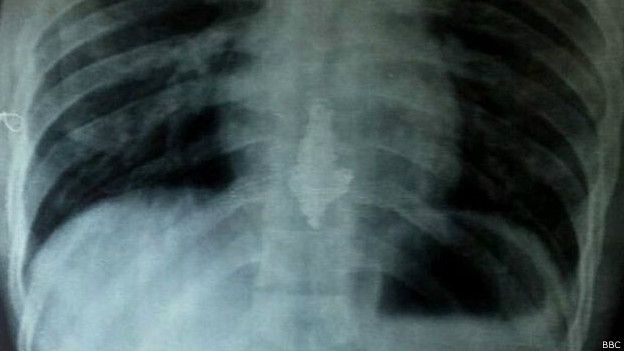

Yadav fue sometido a la dieta después de que las radiografías que se le tomaron mostraron la joya alojada en el esófago.

El collar, que tiene un pendiente, ahora llegó al estómago.

Yavad fue trasladado a un hospital y sometido a una radiografía que reveló el collar dentro de su cuerpo.